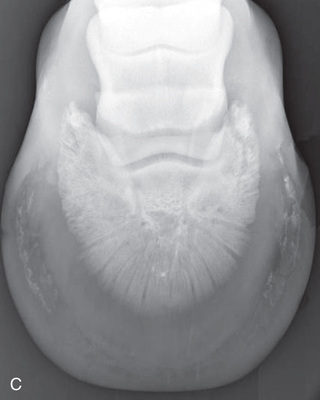

Proper patient preparation is essential to obtain high-quality radiographs and to minimize radiation exposure. The hair coat should be dry, brushed, and cleared of dirt or other debris. If the foot is being radiographed, it is important to prevent overlying shadows superimposed on the field of view. This is especially true of dorsopalmar/dorsoplantar and oblique views. Remove the shoe and trim back any overgrown portions of the foot. Pick and thoroughly clean the sole and clefts, and then pack the sulci adjacent to and in the center of the frog with a substance of similar radiographic opacity, such as Play-Doh, methylcellulose, or softened soap, to eliminate gas shadows due to the grooves of the frog (Fig. 24.2).